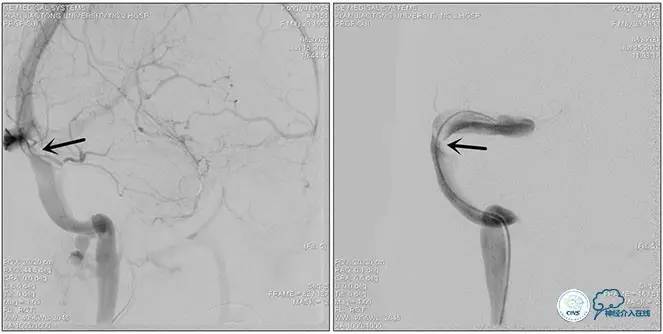

术中右侧ICA造影

右侧ICA斜位及窦内造影

右侧ICA斜位

窦内造影及路图

术中测压:

远端:520mmH2O,

近端:190mmH2O。

治疗方案:

1、8mm×40mm , EverCross球囊扩张;

2、8mm×40mm,Protégé自膨支架成形术。

术后右侧ICA造影

术后远、近端压力差为:0

术后右侧ICA斜位